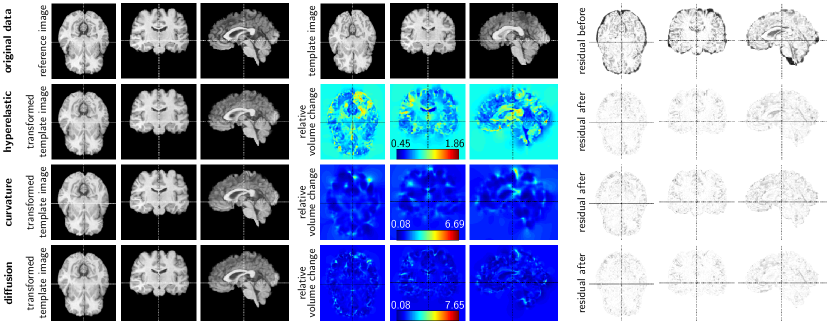

4.5 3D Brain Registration

Experimental Setup

The data is taken from the NIREP repository [19]. We consider the datasets na02 (template image) and na01 (reference image) for our experiments. The grid size for these images is 256×300×256256300256256\times 300\times 256. We downsample these images to a size of 128×150×128128150128128\times 150\times 128 voxels to make the problem computationally tractable for our prototype and the reference implementation. The image domain is defined to be Ω=(0,20)×(0,23.4375)×(0,20)Ω020023.4375020\Omega=(0,20)\times(0,23.4375)\times(0,20). We use SSD as distance measure and a multi-level strategy with 3 resolution levels (32×38×3232383232\times 38\times 32, 64×75×6464756464\times 75\times 64, and 128×150×128128150128128\times 150\times 128). The number of unknowns is 7 372 80073728007\,372\,800 for the finest level.

We evaluate registration performance based on overlap measures evaluated for the label maps associated with the images. The data comes with 32 labels for gray matter regions [19]. We simplify the presentation of our results by only considering the union of these labels to evaluate the performance of our method. We use the Dice coefficient as a measure for registration quality, which has an optimal value of 1. We use a nearest-neighbor interpolation model to transform the label maps with the computed y𝑦y to avoid any additional thresholding.

We limit the evaluation of the determinant of the Jacobian to the foreground (i.e., the brain) in the reference image. We identify this foreground by thresholding; we consider intensities with a value of 0.05 and larger as foreground. We slightly extend this mask by smoothing it with a Gaussian kernel of width 2h22h. A second thresholding step defines the final brain mask used for the evaluation of the Jacobians.

• Proposed (LDDMM): The velocity field is modeled on a slightly larger domain than the image domain to reduce boundary effects; we choose Ωv=(1,21)×(1,24.4375)×(1,21)superscriptΩ𝑣121124.4375121\Omega^{v}=(-1,21)\times(-1,24.4375)\times(-1,21). We consider stationary and non-stationary velocities v𝑣v. We use nt=1subscript𝑛𝑡1n_{t}=1 time intervals for the non-stationary case (which results in two discretization points for the velocity v𝑣v). We use an RK4 method with N=5𝑁5N=5 time steps to compute the characteristics . The push-forward matrix is build using tri-linear hat functions, with a width that corresponds to the voxel size of the image data. We consider the curvature (H2superscript𝐻2H^{2}) and the diffusive (H1superscript𝐻1H^{1}) regularization model. We study registration performance (data mismatch and extremal values of the Jacobians dety𝑦\det\nabla y) as a function of the regularization weight α𝛼\alpha. Once we have found the velocity v𝑣v, we compute the transformation y𝑦y we use to evaluate the performance of our method using N=20𝑁20N=20 time steps. We experimentally found that a shift of γ=0𝛾0\gamma=0 and γ=1E2𝛾1E-2\gamma=$110-2$ yields the optimal rate of convergence for the diffusive and the curvature regularization model, respectively. We set the tolerance for the optimization to tolJ=5E2subscripttol𝐽5E-2\text{tol}_{J}=$510-2$. We use a relative tolerance of 1E11E-1110-1 for the PCG method; we limit the number of Krylov iterations to 50.

• Hyperelastic registration: We experimentally found that regularization weight of α1=100subscript𝛼1100\alpha_{1}=100 (length regularizer), α2=10subscript𝛼210\alpha_{2}=10 (surface regularizer), and α3=100subscript𝛼3100\alpha_{3}=100 (volume regularizer) yields high data fidelity (good mismatch) and well behaved Jacobians. We use this setting throughout our experiments. We set the tolerance for the optimization to tolJ=1E3subscripttol𝐽1𝐸3\text{tol}_{J}=1E-3.

Refer to caption

Fig. 6: Exemplary results for a 3D intensity-preserving registration problem based on MRI datasets of the human brain. The data is taken from the NIREP repository. We show (from left to right) an axial, coronal, and sagittal view of the reference image (dataset na01), the template image (dataset na02), and the residual differences between these two images in the top row. The results correspond to those reported in Table 2. We report results for a map based approach with a hyperelastic regularization model (second row: run #1 in Table 2; α1=100subscript𝛼1100\alpha_{1}=100 (length regularizer), α2=10subscript𝛼210\alpha_{2}=10 (surface regularizer), and α3=100subscript𝛼3100\alpha_{3}=100 (volume regularizer)) [15], and for the proposed method for a non-stationary velocity field (third row: curvature regularization model; α=10𝛼10\alpha=10; run #10 in Table 2; bottom row: diffusive regularization model; α=300𝛼300\alpha=300; run #13 in Table 2). For each of these methods we show (from left to right) an axial, a coronal, and a sagittal view of the deformed template image, a map for the relative volume change, and the residual differences between the transformed template image and the reference image after registration. We also display the color bar and the maximal and minimal values for the maps for the relative volume change.